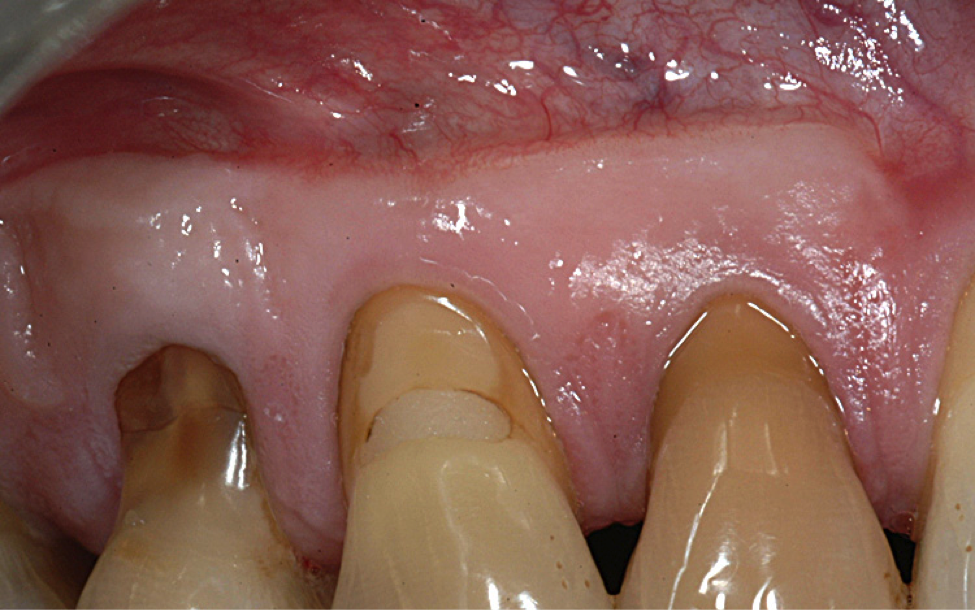

A male patient in his 30s presented for treatment of increasing recession he had had over his lifetime. Upon examination, a complete lack of gingiva on the facial of tooth No. 6 was observed. Although he had about 1.5 mm of gingiva on the facial of tooth No. 7 (Figure 4), both teeth probed to 3 mm. This indicated an absence of attached gingiva on the facial of these teeth in addition to increasing recession.

With a low lip line, the patient was not concerned about esthetics, and he was not experiencing root sensitivity. It was determined and agreed that a FGG was the best option for him in order to increase the amount of gingiva and limit further recession.